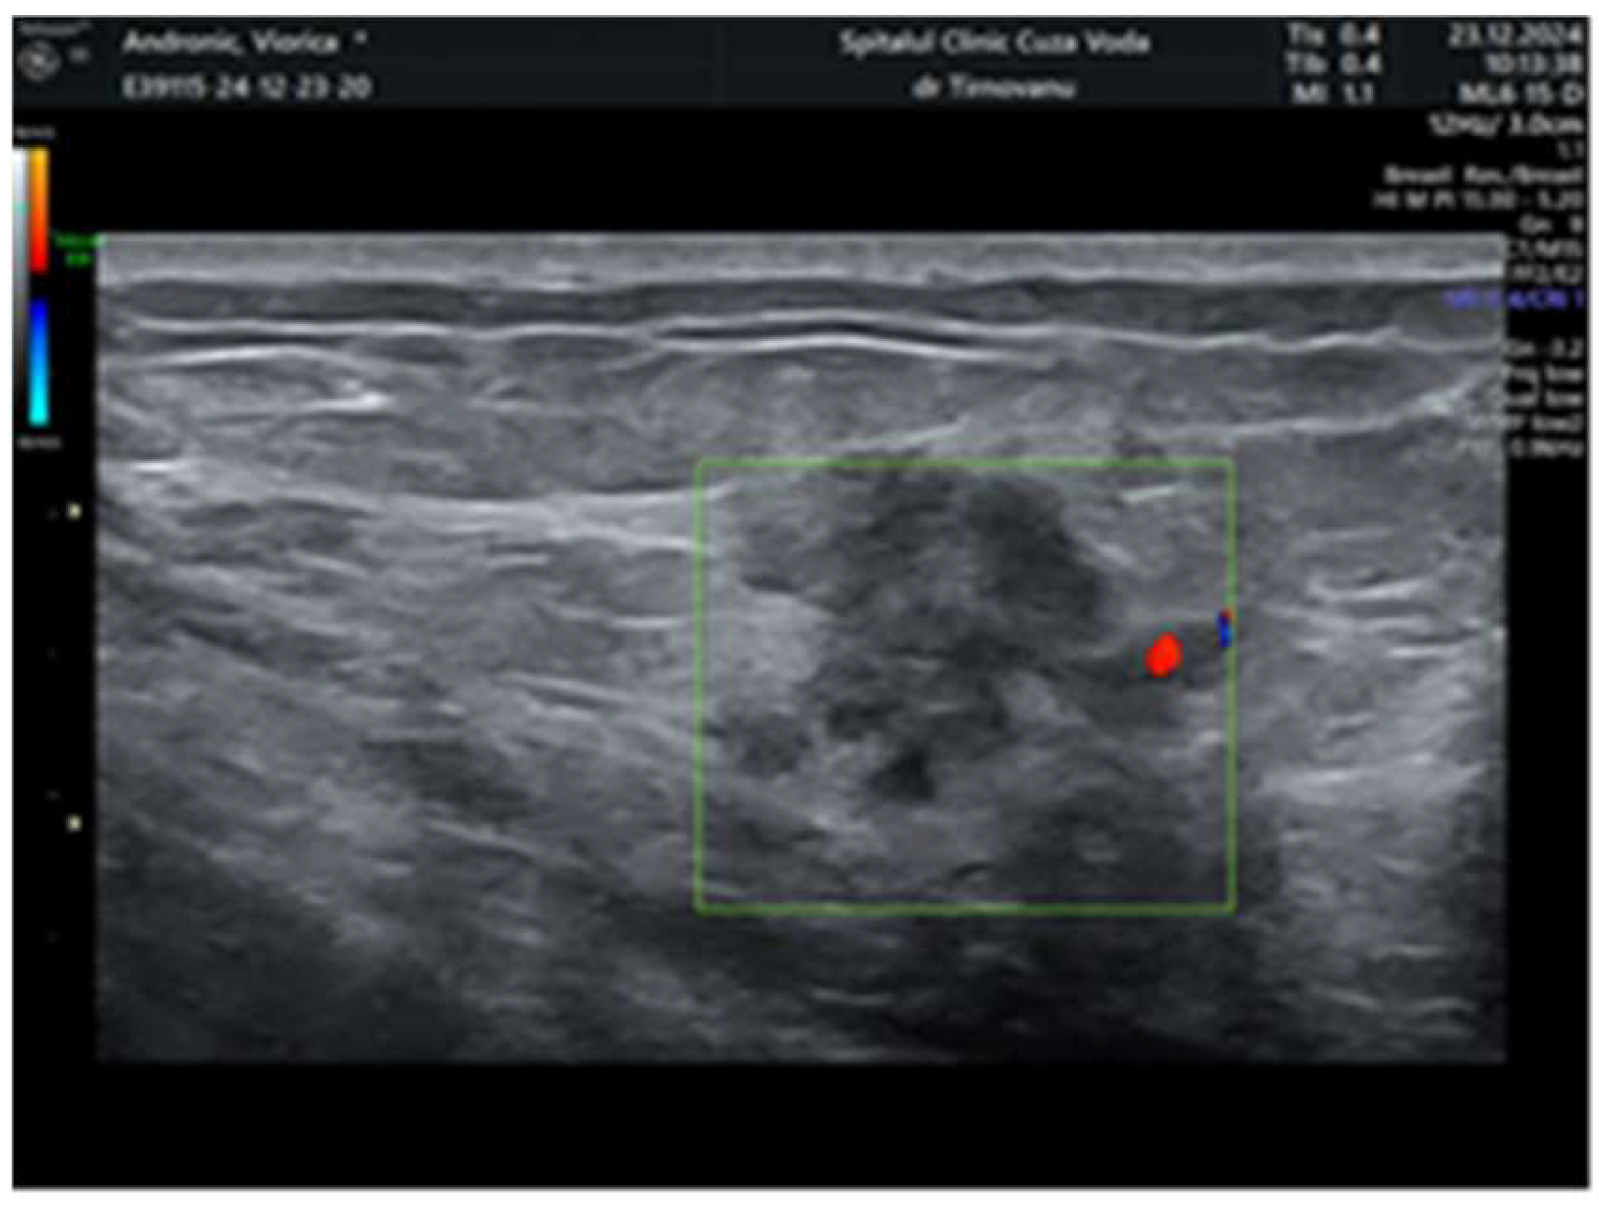

2. Case Report